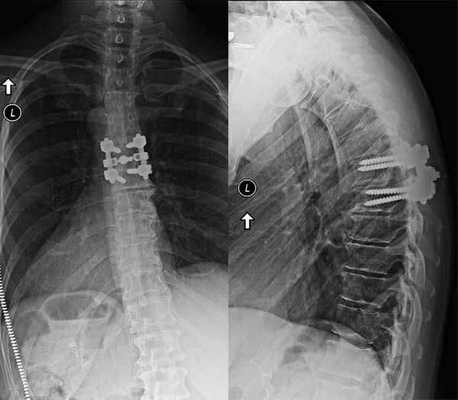

Техника декомпрессивной операции

Сразу отметим, что такой хирургический подход определенным образом чреват дестабилизацией ламинэктомированных костных тел. Поэтому довольно часто возникает необходимость в проведении ламинэктомии с фиксацией позвонков, то есть совместно со спондилодезом. А это означает, что по завершении основного процесса хирургии пара или несколько позвонков могут быть скреплены между собой специальной металлической пластиной, возможно, дополнительно понадобится произвести трансплантацию костной ткани, взятой у пациента из подвздовшной кости. Благодаря произведенной фиксации соединенные элементы хоть и будут обездвижены, каких-либо существенных ограничений подвижности люди, как правило, не испытывают.

Сращение позвонков на рентгене.